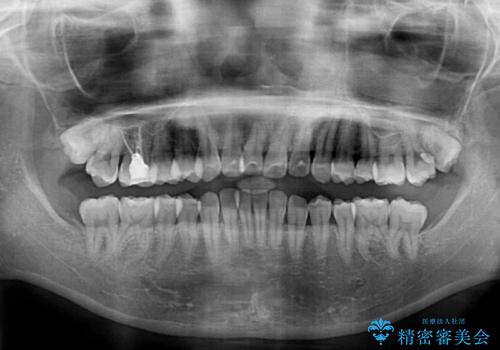

- 上下前歯のデコボコを気にして来院された患者様です。

インビザラインによる上下歯列の側方拡大と後方移動、IPR(歯と歯の間を削る)にるスペースの獲得により歯列を整えることとしました。